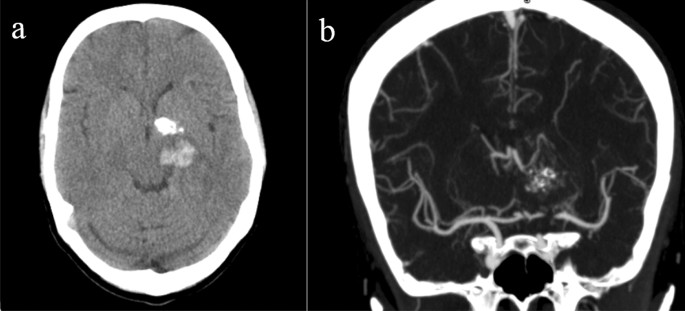

A 53-year-old man is brought to the emergency department for confusion. He was in his usual state of health until about 3 hours ago when he tried to use his sandwich to turn off the TV. He also complained to his wife that he had a severe headache. Past medical history is notable for hypertension, which has been difficult to control on multiple medications. His temperature is 36.7°C (98°F), the pulse is 70/min, and the blood pressure is 206/132 mm Hg. On physical exam he is alert and oriented only to himself, repeating over and over that his head hurts. The physical exam is otherwise unremarkable and his neurologic exam is nonfocal. The noncontrast CT scan of the patient's head is shown and reveals an acute intraparenchymal hemorrhage in the basal ganglia. Which of the following diagnostic tests would be most helpful in determining the underlying cause of this patient's hemorrhage?